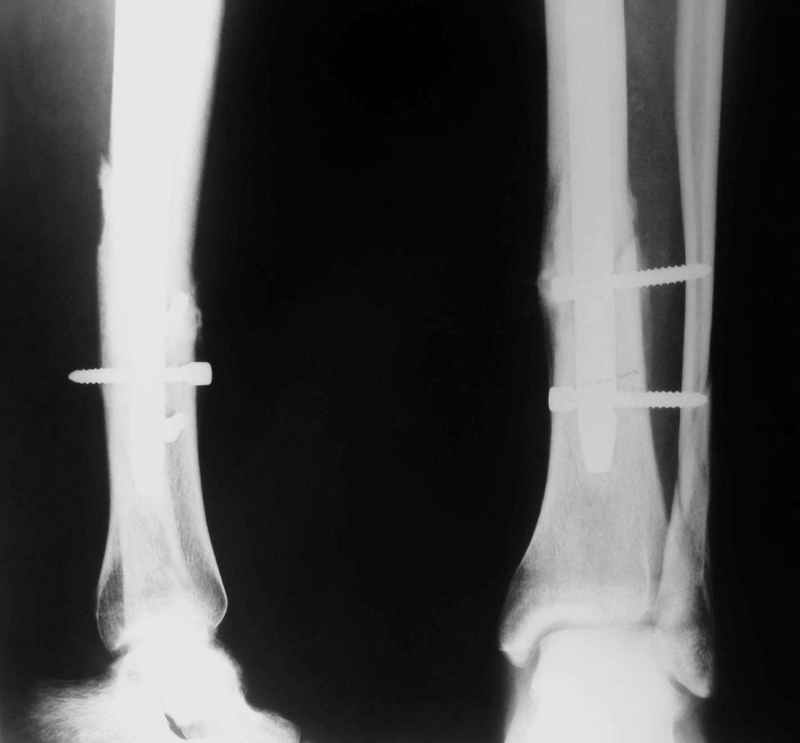

Не удается отправить первичные снимки. А что скажите по имеющимся?!

Выполненный остосинтез нестабилен. Штифт надо заменить по "размеру" на солидный, дистльно три запирающих винта. Успехов!

Перелом спиральный, то есть низкоэнергетический, так что со сращением дело обстоит уже неплохо, лишь бы "костоеда" не развилась. Отломки выглядят уже стабилизированными костной мозолью, так что довводить винты, наверно, уже незачем. Разве что при клинической оценке подвижность еще есть - тогда можно для стабилизации наложить простейший аппарат, не опасаясь контакта его элементов с гвоздем, поскольку места в дистальном метафизе оставлено более чем достаточно.

С Александром согласен, нет необходимости делать дополнительные усилия для сращения, не большая компрессия аппаратом из двух колец и полная нагрузка доделает работу.

Уже имеется какое-то сращение. А в этих условиях выполнить реостеосинтез гвоздём не дольше, чем "накинуть" аппарат из двух колец. Ходить можно сразу с полной нагрузкой, да и качество жизни пациента без аппарата лучше.